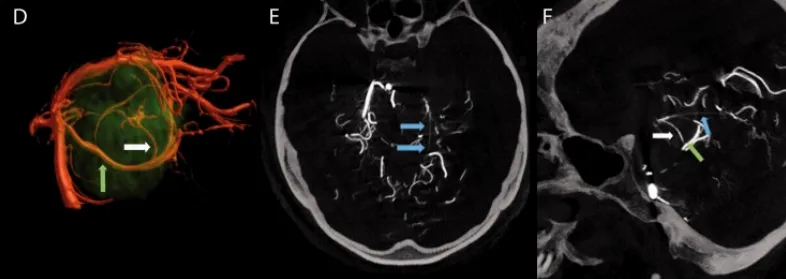

2、3D数字减影血管造影(DSA)

由于常规的二维血管造影无法检测到肿瘤的染色,因此进行了3D数字减影血管造影(DSA)的双角度检查。通过对比注射碘对比剂进入左侧椎动脉前后的情况,诊断出了起源于脉络膜动脉(SCA)并向肿瘤供血的丰富动脉网络,即小脑幕动脉。随后,对此动脉进行的选择性导管插入和选择性血管造影进一步证实了其供血起源。

3、术前栓塞

鉴于该动脉源自手术入路对侧的硬脊膜内动脉,且位于肿瘤的后方,手术中对其进行控制将十分具有挑战性。因此,福教授识别并标记主要供血动脉,通过使用1毫升氰基丙烯酸酯胶稀释在4毫升碘油中的混合溶液进行栓塞,血管造影显示结果令人满意,且未出现任何并发症。

选择性栓塞导致肿瘤后部部分去血管化(蓝色箭头),这有助于手术摘除。肿瘤的前部仍然由海绵窦内ICA(internal carotid artery,ICA)的分支供血(绿色箭头),在手术过程中这些分支被凝固处理。